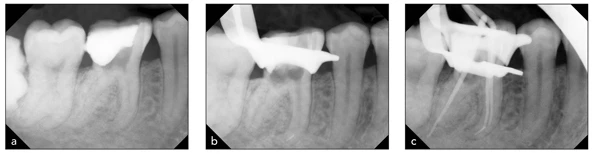

May mắn là chỉ cần những thao tác nhẹ nhàng nhất cũng dễ dàng làm sạch vùng chóp. Việc uốn cong đầu file với cả file thép không gỉ và file NiTi đều làm giảm nguy cơ tạo khấc, nhưng cũng không thể loại bỏ hoàn toàn rủi ro đó nếu thao tác không đúng cách và trên thực tế file có thể gãy một cách bất ngờ (Hình 21-3).

Hình 21-3: Sửa soạn ống tủy một cách thô bạo bằng trâm quay cứng có thể gây tai biến, nhưng quan trọng hơn, có thể dẫn đến gãy file ở phần chóp. (a) Hình ảnh sau khi mở tủy. (b) Hình ảnh cho thấy đoạn file gãy ở ống tủy gần trong nằm dưới chỗ cong. (c) Đoạn file gãy không thể lấy ra được và nha sĩ đã cố gắng hàn ống tủy xung quanh đoạn file đó.